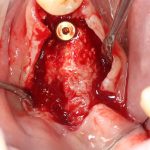

Кстати, обрати внимание на ширину альвеолярного гребня (левая картинка). Она чуть меньше 3 мм. Это объясняет, почему я засомневался в возможности установки имплантатов одновременно с остеопластикой. Понятно и без КЛКТ.

Наперво, мне нужно удалить разрушенный зуб и получить костный аутотрансплантат.

Для получения костного блока, мы открываем донорскую зону, наружную косую линию нижней челюсти.

Возвращаемся к основной операционной области. Еще раз посмотрим на альвеолярный гребень, поофигеваем от его ширины и моих грандиозных планов: